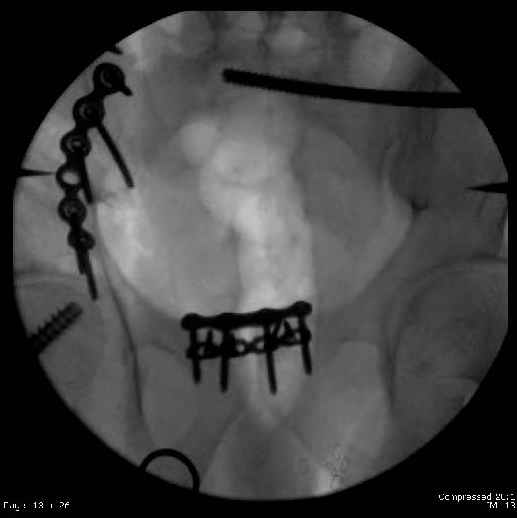

Here are the postop fluoros.

First exposed symphysis & clamped w/Faraboeuf as close to anatomic as possible.

Then extended to R ilioinguinal,really just the lateral window.

Reduced the triangular wedge piece of iliac wing to posterior intact ilium (crescent), held w/k-wire, then used 3-hole push plate to keep from moving, lagged from lat-med w 3.5 screw.

Then 6-hole plate along brim with 1 screw in R sacral ala. Then lagged 2 screws along crest A --> P. finally 10-hole plate along inner aspect of crest. R posterior ilium still a bit stepped off.

Symphysis then 'fine-tuned' & reduced as close as possible to anatomic (but, still with forward rotation of R hemipelvis - or, is it extension?) Accepted that amount of deformity and plated symph

with 4-hole symphyseal plate.

Fluoroed L SI joint and it seemed stable, but wide. So, applied c-clamp to try to squeeze down L SI joint (and note, on the last slide attached, that it's still wide), and got it closer. Single perc Iliosacral screw 40mm thread.

Applied second plate anteriorly on symphysis as I wasn't confident L SI was as stable as it could be and wanted to protect it better.

Thoughts? Thanks for the advice, it's appreciated.